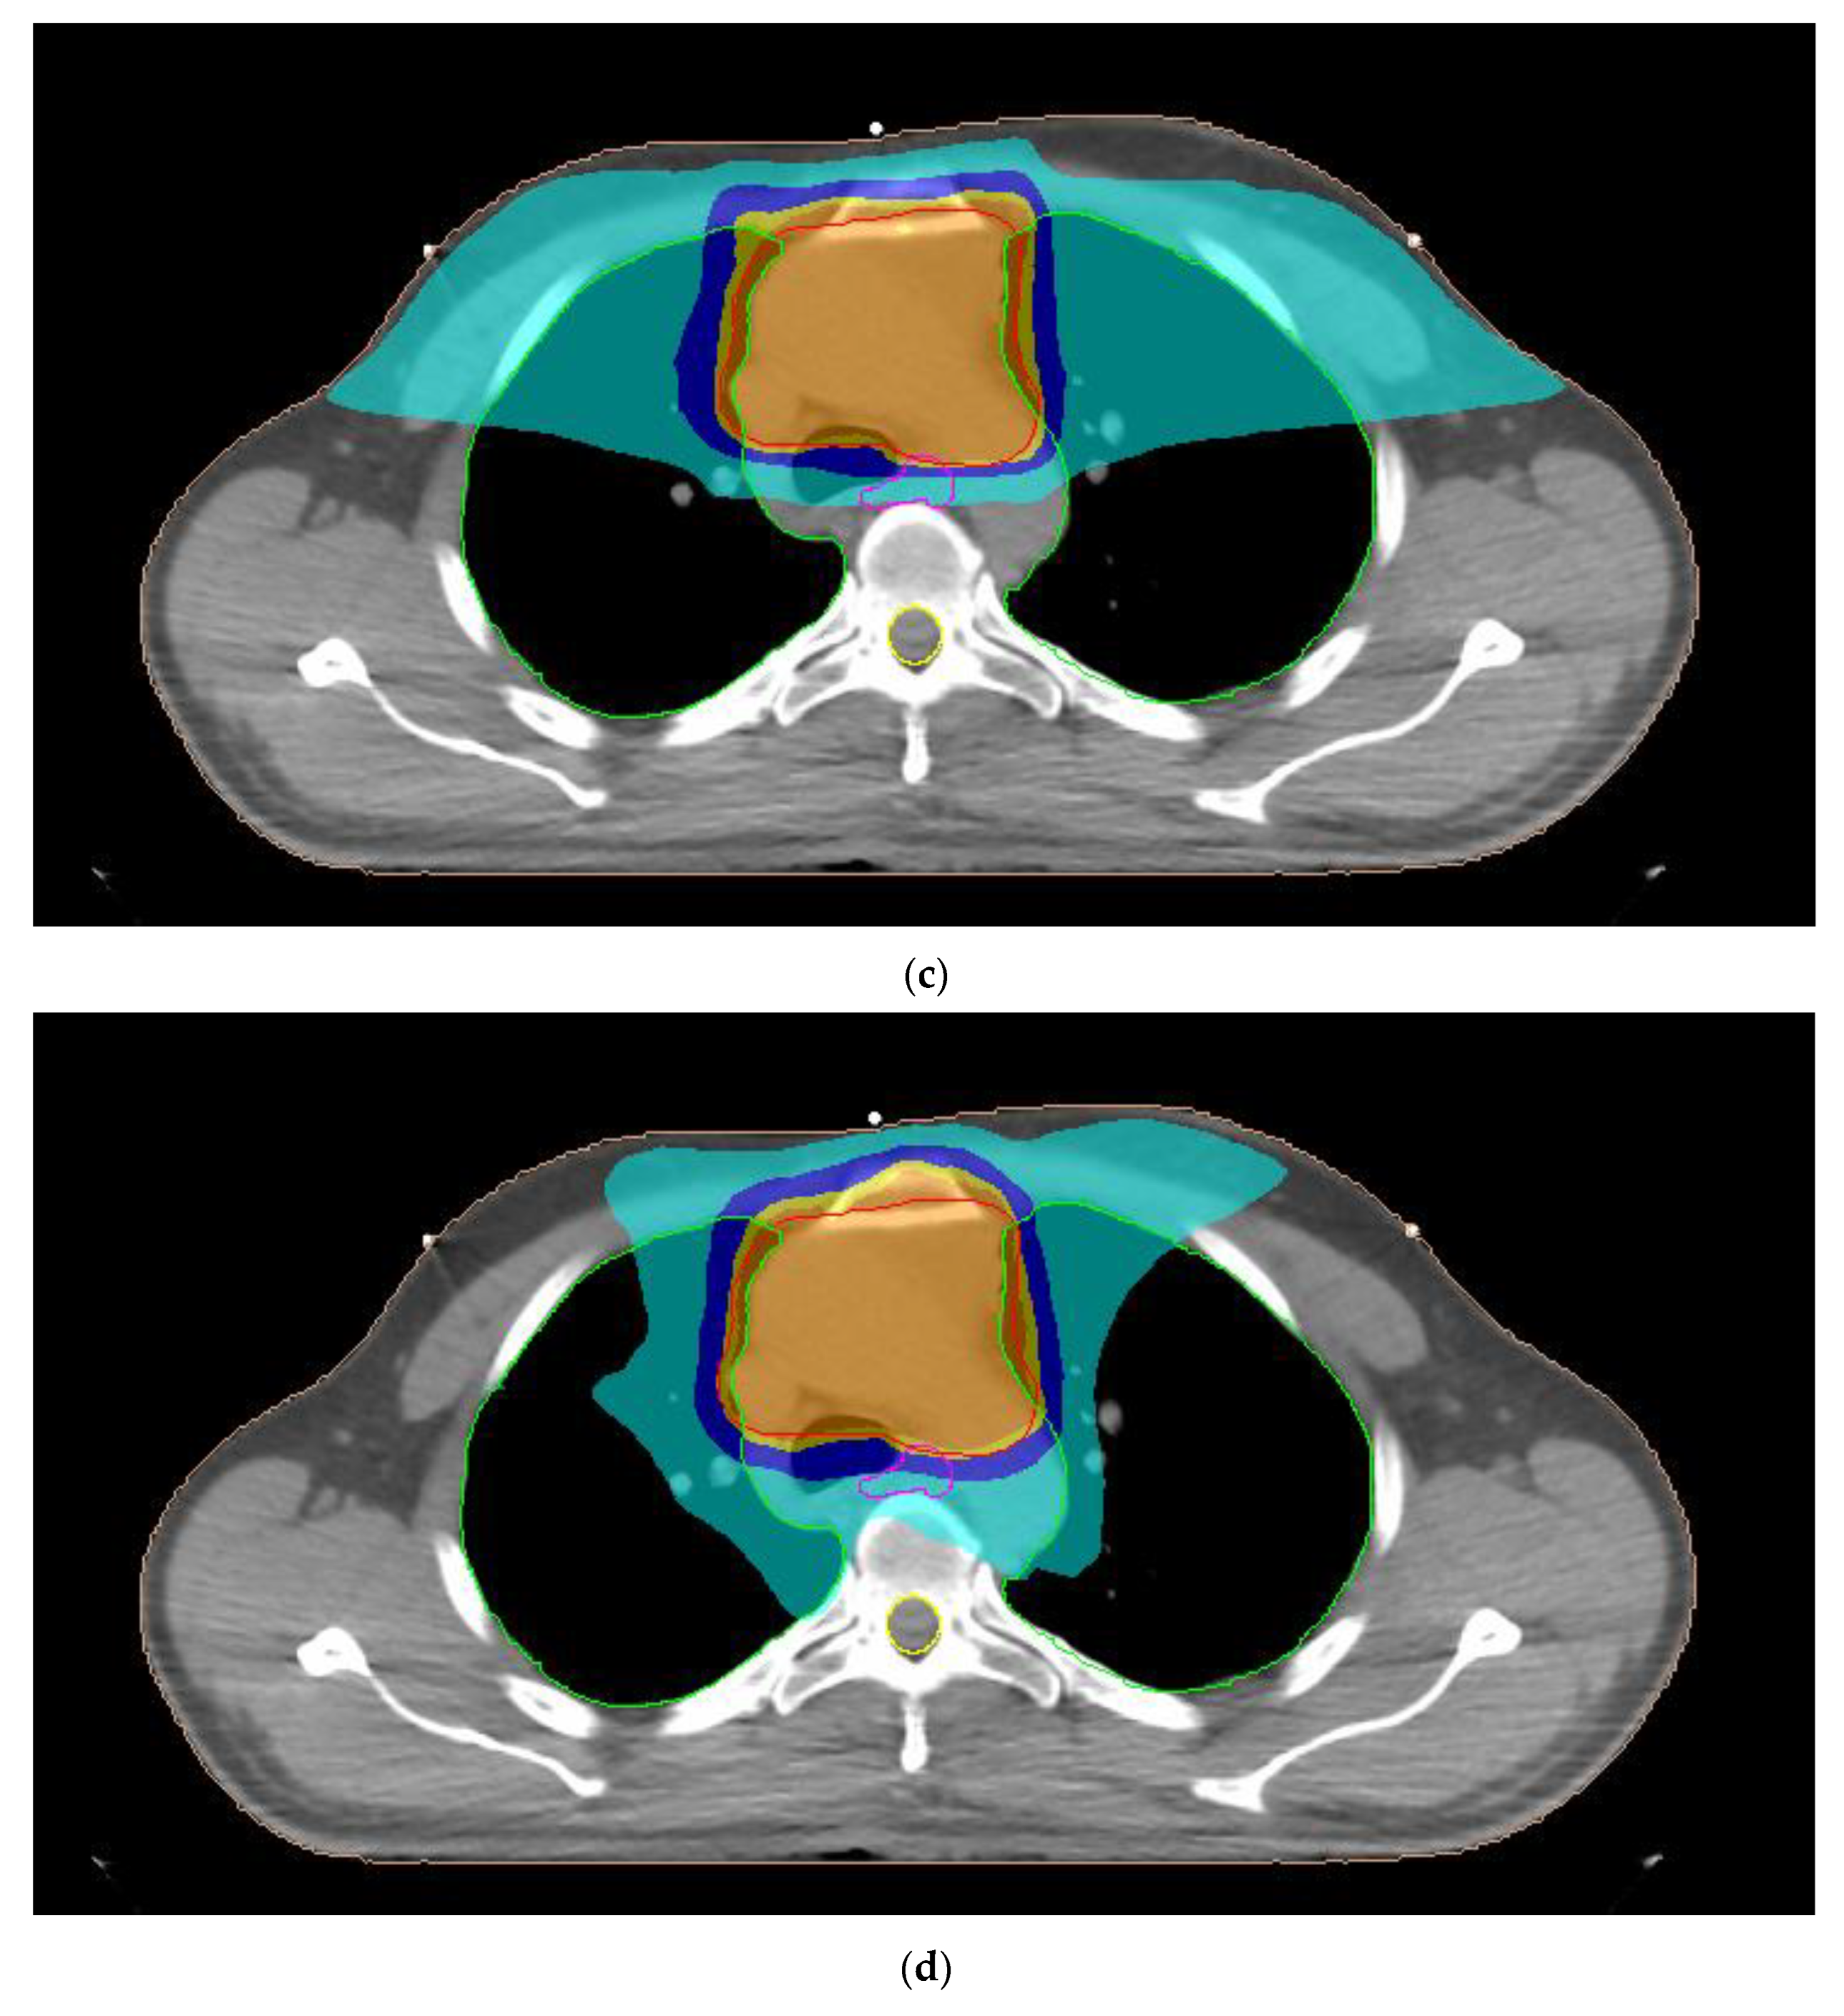

2.2. Treatment Planning